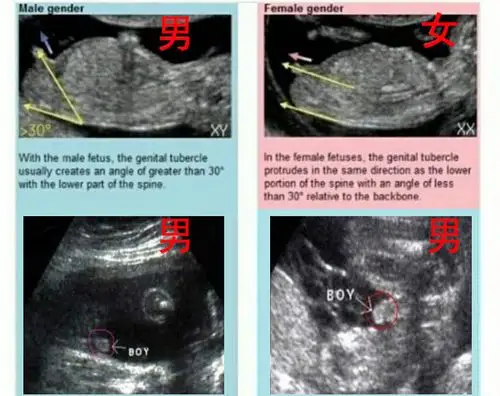

皮肤开始出现毛囊,肝脏开始活动头部占胎儿身长的一半外部生殖器官

孕 周二维超声示胎儿男性外生殖器,呈「郁金香征」